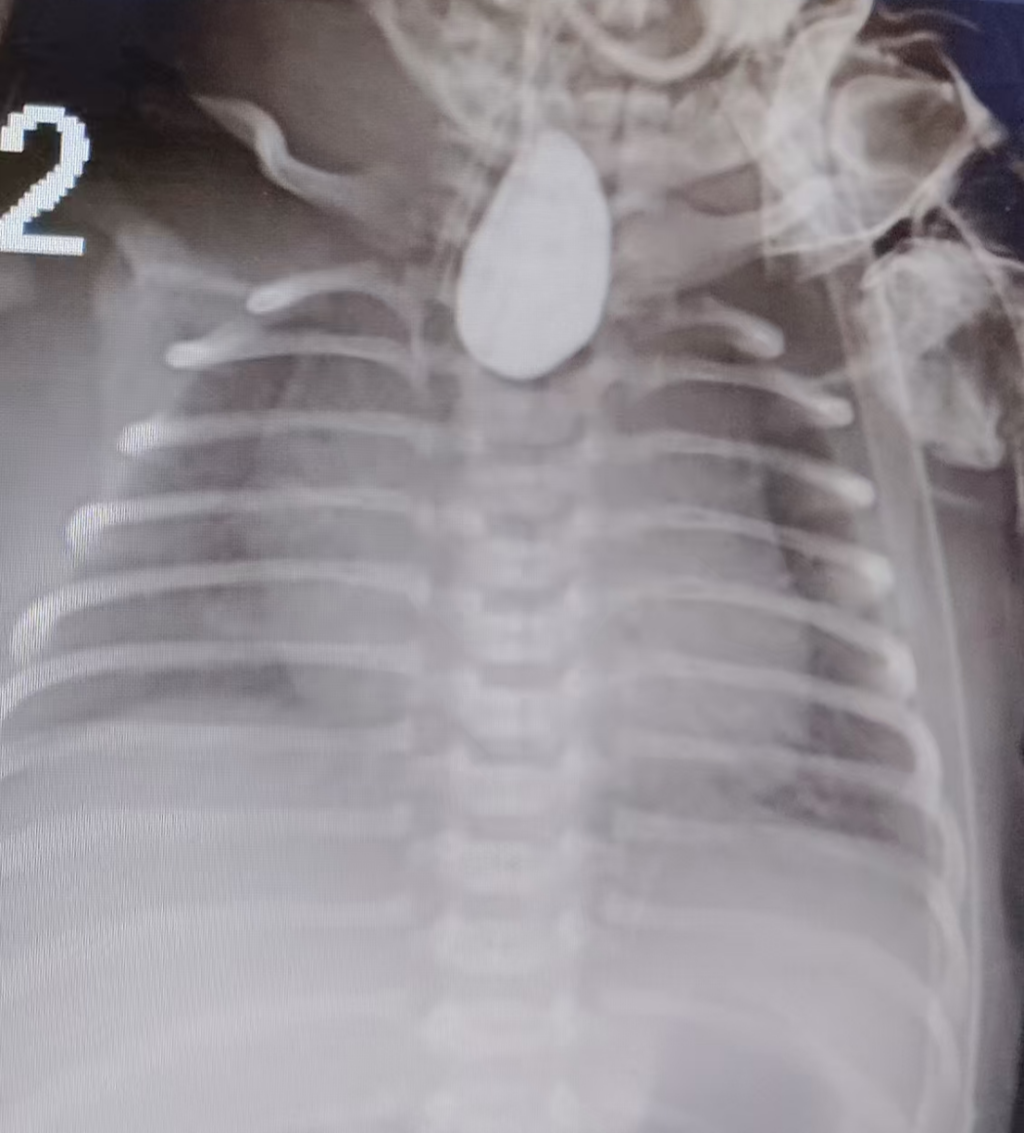

服用的造影剂集聚在“不通”的食管盲端内